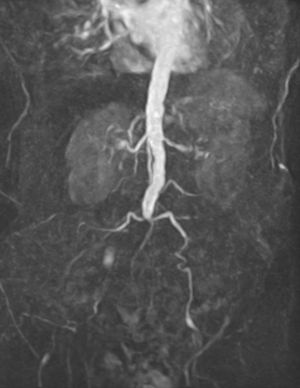

혈관외과는 혈관 질환을 다루는 외과 분야로, 1970년대에 전문 분야로 인정받기 시작했다. 혈관외과는 동맥, 정맥, 림프관과 관련된 질환을 진단하고 치료하며, 수술, 혈관 내 치료, 약물 치료 등 다양한 방법을 사용한다. 초기에는 동맥 및 정맥 수술에 중점을 두었으나, 현재는 최소 침습적 기술이 강조되고 있다. 혈관외과는 대동맥류, 동맥 박리, 말초 동맥 질환, 정맥류, 심부 정맥 혈전증 등 다양한 혈관 질환을 관리하며, 혈액 투석 접근 관리 및 혈관 외상 관리에도 관여한다. 미국, 호주, 뉴질랜드 등 여러 국가에서 혈관외과는 독립적인 전문 분야로 인정받고 있으며, 관련 학회와 수련 과정을 통해 전문 인력을 양성하고 있다.

PAD 진단은 병력, 신체 검사, 의학 영상 ( 발목-상완 지수, 도플러 초음파, 컴퓨터 단층 촬영 혈관 조영술 등)을 종합하여 이루어진다. 치료는 개별화되며, 혈관 성형술, 스텐트 삽입, 죽상 동맥 절제술, 내막 절제술, 혈관 우회술 등 내과적 치료, 혈관 내 중재술, 개방형 수술 옵션을 포함한다.